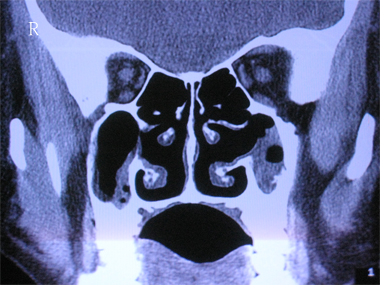

以下是引用zhangzhongshou在2007-5-26 23:02:00的发言:[br]左侧上颌窦霉菌感染,右侧慢性上颌窦炎(粘膜肥厚为主)。